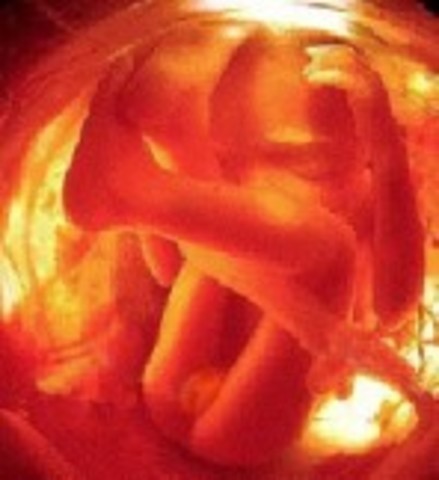

• Week 20: The Halfway Point

Week 20: The Halfway Point

The movements of the baby can most likely be felt by the mother now. The skin is becoming thicker and hair is also starting to grow on the rest of the fetus' body. The baby also weighs about 11 ounces and is around 7 inches.